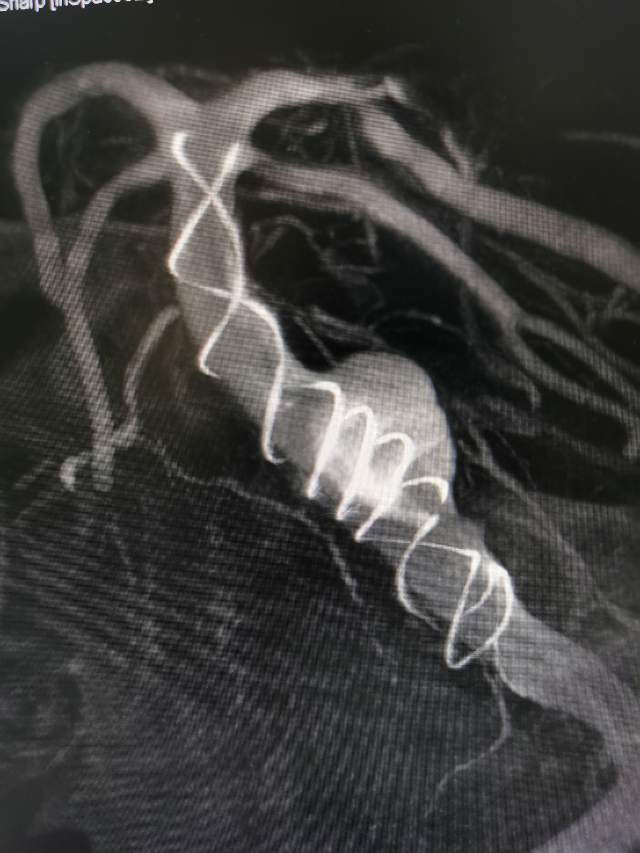

椎基底动脉冗长扩张症,是最棘手最复杂的脑血管病之一。患者从外地千里迢迢(3900余公里,仅高铁41小时)赶来东方医院诊治,期间症状不断加重(图2非真实大小)。术后一周复查:1、右侧肢体肌力明显改善;2、右侧肢体和枕部麻木症状明显改善;3、饮水呛咳缓解;4、共济失调明显改善;5、流涎消失;6、消失的味觉再次恢复。术后一周复查:血管修复良好(图5)。期待患者早日康复,早日奔赴工作岗位,保一方平安。